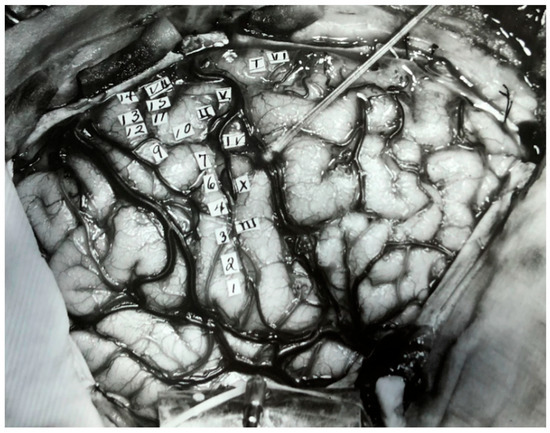

- Leblanc, R. Wilder Penfield and Academic Neurosurgery in North America: 1934–1945. Can. J. Neurol. Sci. 2021, 1–10. [Google Scholar] [CrossRef]

- Rech, F.; Herbet, G.; Gaudeau, Y.; Mézières, S.; Moureau, J.-M.; Moritz-Gasser, S.; Duffau, H. A Probabilistic Map of Negative Motor Areas of the Upper Limb and Face: A Brain Stimulation Study. Brain 2019, 142, 952–965. [Google Scholar] [CrossRef]